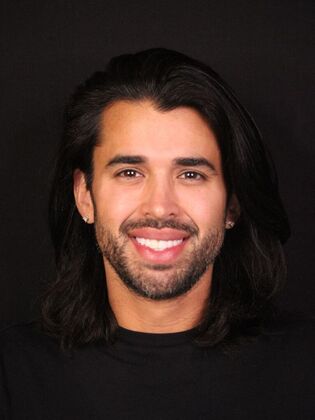

Full Mouth Rehabilitation: Eric

Description

Eric had pre-existing veneers he was wanting to have upgraded and one had recently broken while out of state. Once we consulted, we discovered Eric's bite was destructive leading to frequent headaches, popping & clicking in the jaw joints, and overall jaw fatigue. We discussed upgraded his porcelain restorations and opening his bite in order to correct his TMJ dysfunction. Treatment was completed using TENS and separated into two appointments for the top and two appointments for the bottom arch several weeks apart. Now, Eric is TMJ dysfunction free!